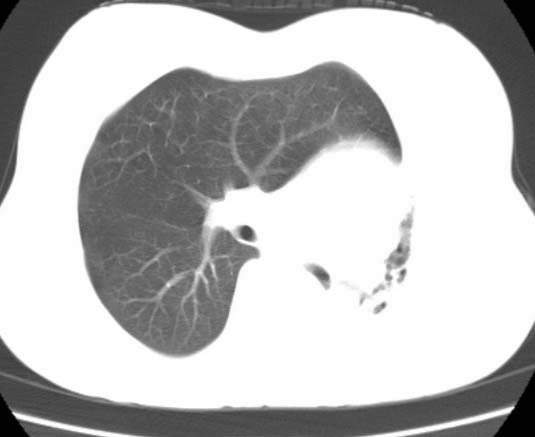

标题: CT25648:求教:是肺发育不全还是结核?

女  20岁。一月前咳血,诊“肺结核”抗痨治疗一月后,咳血停止,现复查。病人精神好。前后ct片对比未见明显变化。既往体检“正常”

1)考虑左肺结核并肺不张、支气管扩张。2)纵隔疝。

考虑左肺结核,左肺毁损,纵膈左偏,既往体检正常不可靠,tb一个月也不会这个样子的,有钙化,应该病程较长,冰冻三尺非一日之寒!

考虑左肺结核,左肺毁损,纵膈左偏,既往体检正常不可靠,tb一个月也不会这个样子的,有钙化,应该病程较长,冰冻三尺非一日之寒